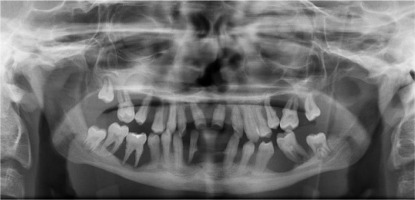

When he was 5 years of age the intraoral examination revealed incomplete primary dentition with five missing teeth, marginal gingivitis, interdental papilla hypertrophy, carious lesions in seven primary teeth, and one permanent tooth of various degrees of advancement for conservative treatment (Fig. 1). The patient was qualified for simultaneous dental treatment under general anesthesia. A panoramic radiograph picture was taken showing the advanced destruction of the alveolar bone in the maxilla and the alveolar part of the mandible. Three primary teeth were completely devoid of bone base. The roots of the lower incisors were only half of their normal length (Fig. 2). Under antibiotic protection (amoxicillin with clavulanic acid at a dose of 30 mg/kg), professional removal of dental plaque and conservative treatment of teeth extraction of four primary teeth with complicated caries and periodontitis were performed. The patient was provided with permanent dental care.